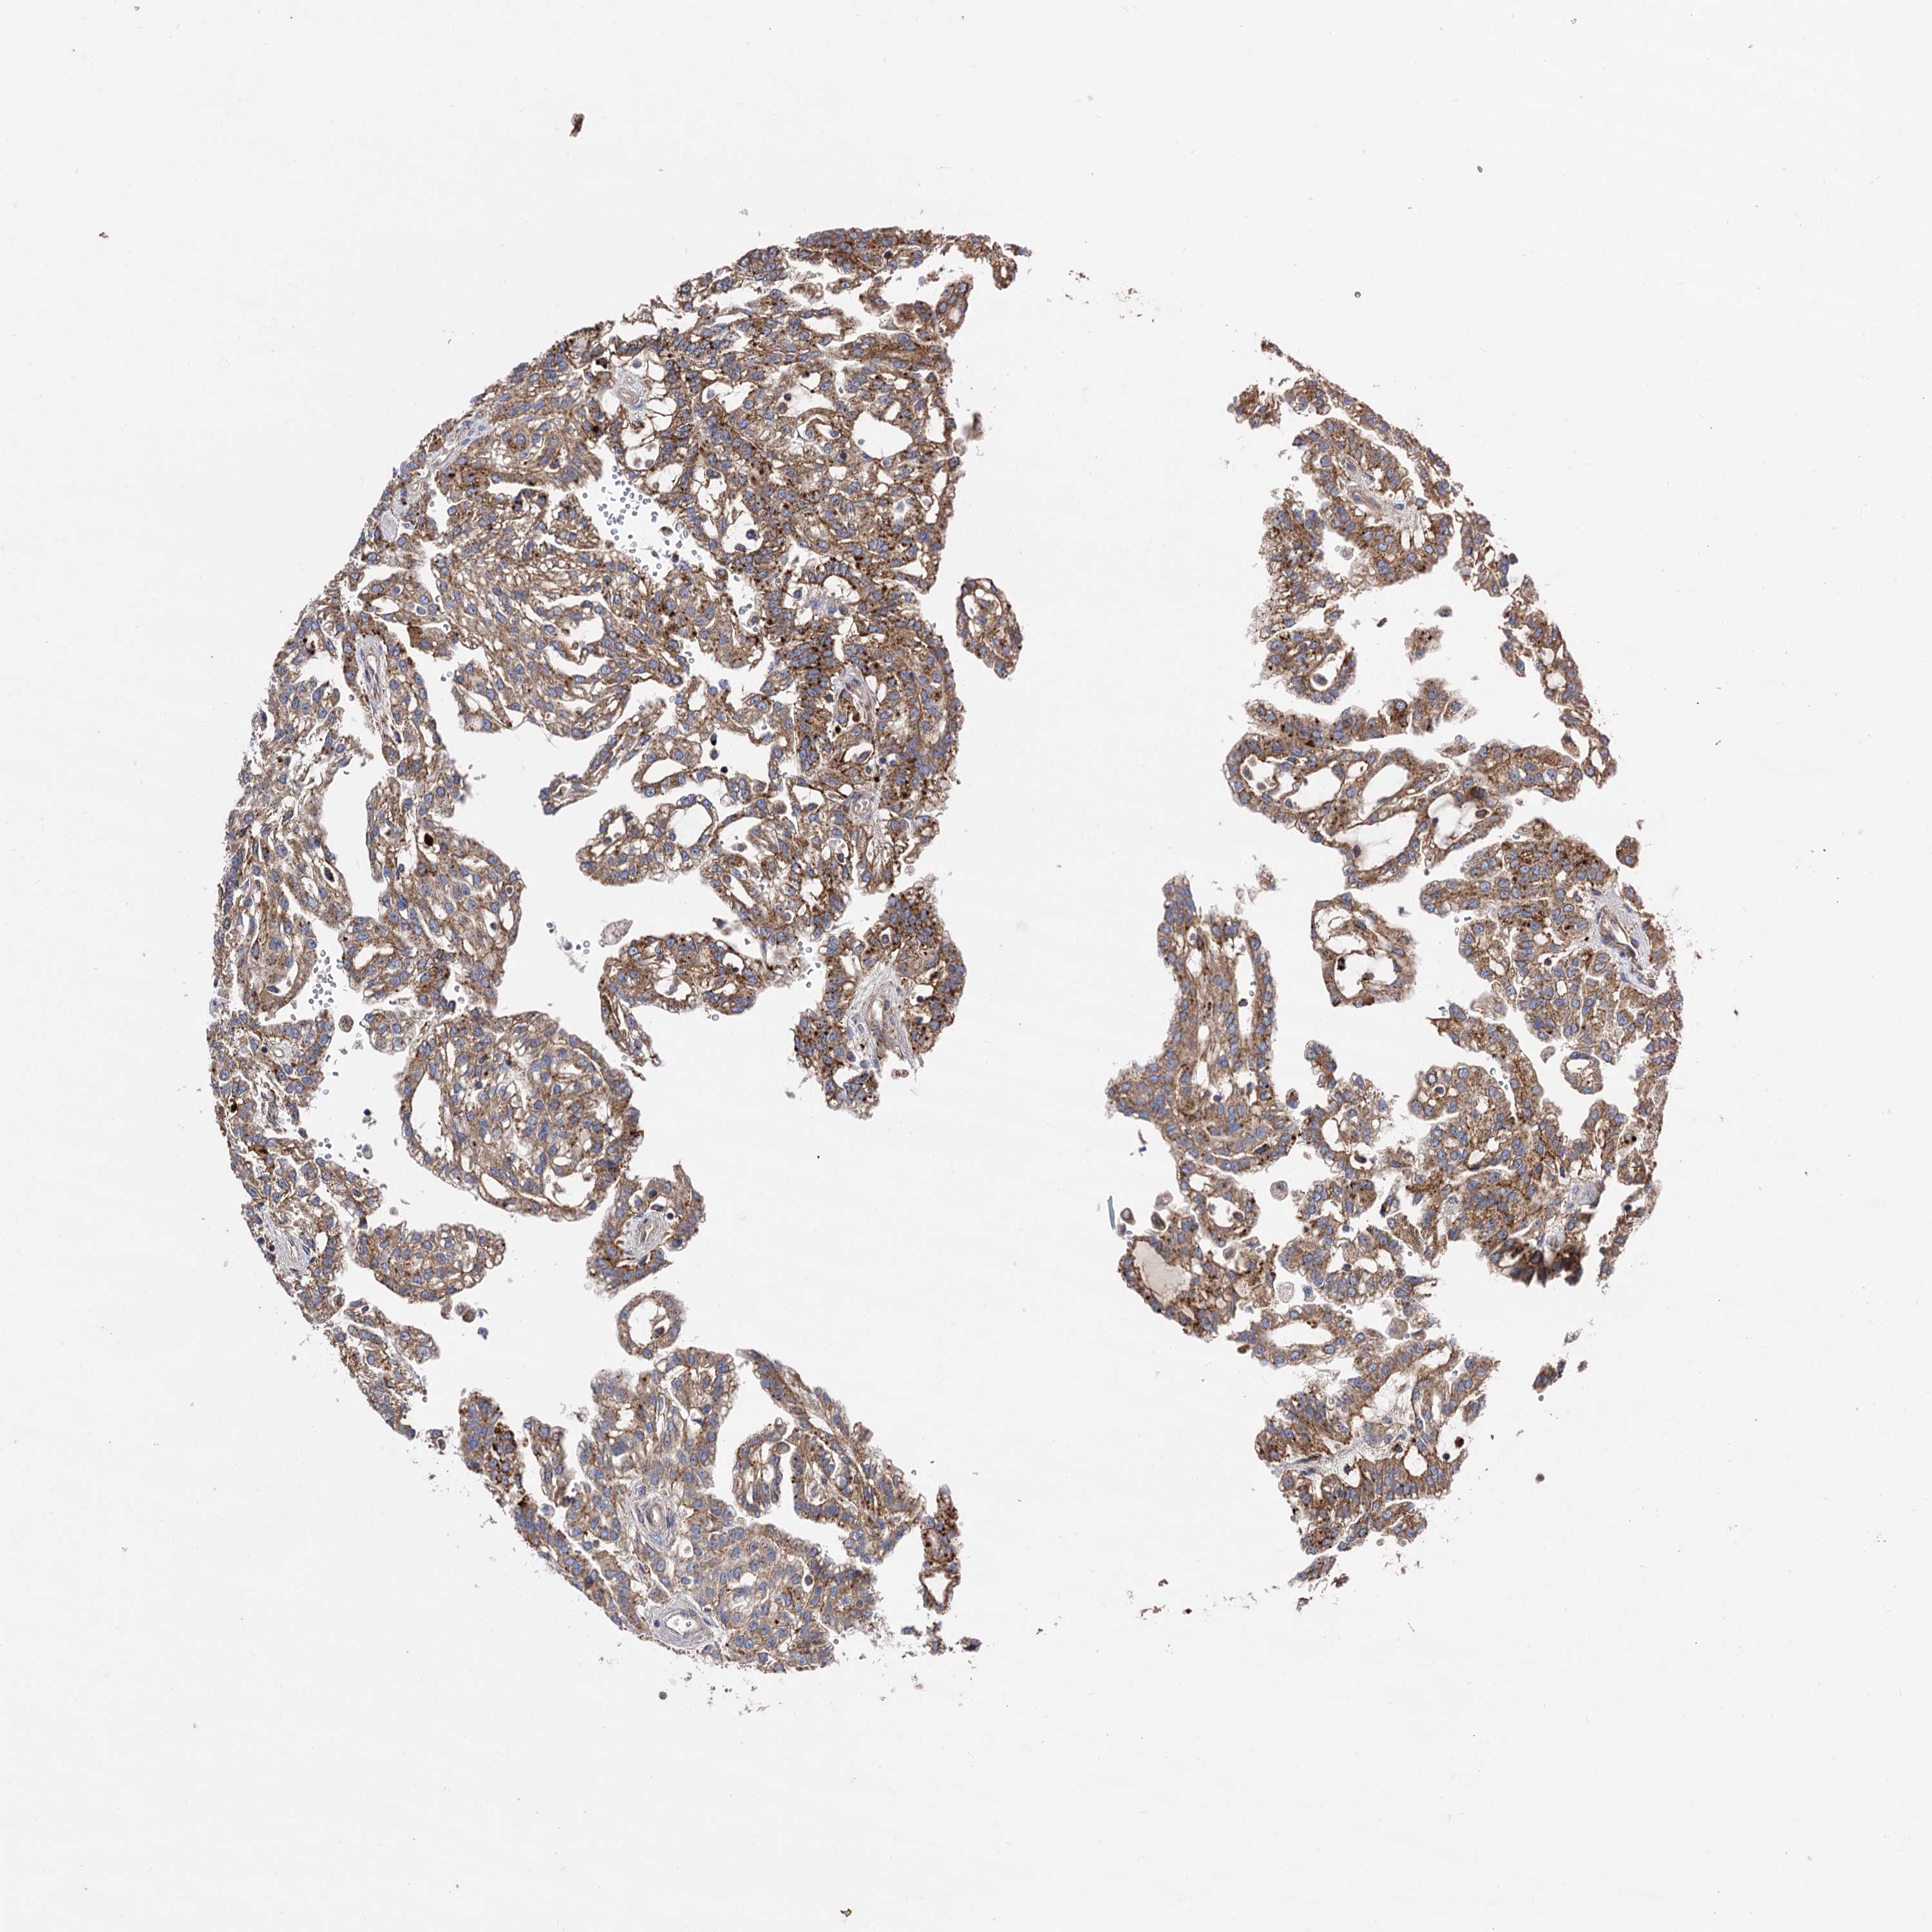

KIDNEY RENAL CLEAR CELL CARCINOMA (TCGA) - Interactive survival scatter ploti

The Survival Scatter plot shows the clinical status (i.e. dead or alive) for all individuals in the patient cohort, based on the same data that underlies the corresponding Kaplan-Meier plots. Patients that are alive at last time for follow-up are shown in blue and patients who have died during the study are shown in red.

The x-axis shows the expression levels (FPKM) of the investigated gene in the tumor tissue at the time of diagnosis. The y-axis shows the follow-up time after diagnosis (years). Both axes are complimented with kernel density curves demonstrating the data density over the axes. The top density plot shows the expression levels (FPKM) distribution among dead (red) and alive patients (blue). The right density plot shows the data density of the survived years of dead patients with high and low expression levels respectively, stratified using the cutoff indicated by the vertical dashed line through the Survival Scatter plot. This cutoff is automatically defined based on the FPKM cutoff that minimizes the p-score. The cutoff can be changed by dragging the vertical line or by entering a cutoff value in the square labeled "Current cut-off".

Under the Survival Scatter plot the p-score landscape (black curve; left axis) is shown together with dead median separation (red curve; right axis). Dead median separation is the difference in median mRNA expression between patients who have died with high and low expression, respectively. It is calculated as follows: median FPKM expression of dead patients with high expression - median FPKM expression of dead patients with low expression. This is intended to aid the user in visually exploring custom cutoffs and the associated p-scores and dead median separation.

Individual patient data is displayed and can be filtered by clicking on one or more of the category buttons on the top of the page. Categories describing expression level and patient information include: high, low, alive, dead, female, male and tumor stages. The scale of the x-axis can be toggled between linear and log-scale by clicking on the "x log" button. Mouse-over function shows TCGA ID, patient information and mRNA expression (FPKM) for each patient.

& Survival analysisi

Kaplan-Meier plots summarize results from analysis of correlation between mRNA expression level and patient survival. Patients were divided based on level of expression into one of the two groups "low" (under cut off) or "high" (over cut off). X-axis shows time for survival (years) and y-axis shows the probability of survival, where 1.0 corresponds to 100 percent.

IQCH is potential prognostic, high expression is favorable in Kidney Renal Clear Cell Carcinoma (TCGA)

Best expression cut offi

Based on the FPKM value of each gene, patients were classified into two groups and association between prognosis (survival) and gene expression (FPKM) was examined. The best expression cut-off refers the FPKM value that yields maximal difference with regard to survival between the two groups at the lowest log-rank P-value. Best expression cut-off was selected based on survival analysis .

When clicking on this number, the vertical dashed line indicating cut-off, the interactive survival plot, and the Kaplan-Meier curve will be adjusted to show results based on the best expression cut-off.

: 0.89

TCGA RNA samplesi

RNA-seq data is reported as average FPKM (number Fragments Per Kilobase of exon per Million reads), generated by the The Cancer Genome Atlas (TCGA) .

Normal distribution across the dataset is visualized with box plots, shown as median and 25th and 75th percentiles. Points are displayed as outliers if they are above or below 1.5 times the interquartile range. FPKM values of the individual samples are presented next to the box plot.

Average pTPM 1.1

Number of samples 521